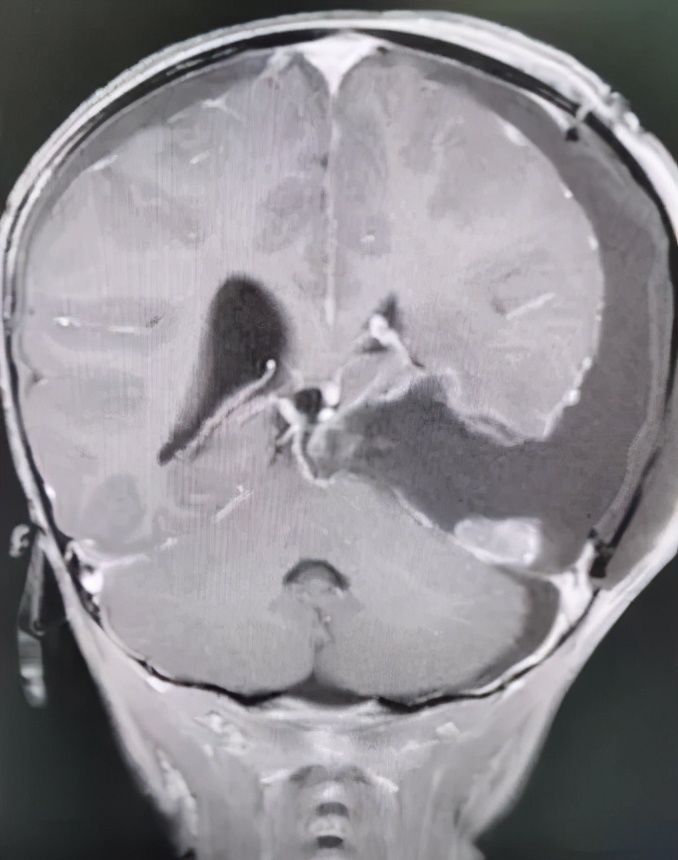

术后MR显示:肿瘤被全切除,脑干也复位了